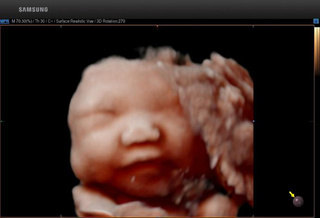

1、 全方位、多角度、图像更清晰

5D超声能够全方位、多角度评估胎儿生长发育情况,广泛应用于胎儿染色体异常所致畸形(NT测量)、胎儿长骨畸形、胎儿心脏畸形、胎儿中枢神经系统畸形等产前筛查的各个领域。

5D智能超声通过大样本的数据分析,智能识别胎儿产前筛查所需多种标准切面,自动进行多项数据测量。对胎儿畸形的早期诊断提供比传统四维彩超更精确的数据!

↓↓胎儿颈项透明层智能识别分析技术 ↓↓胎儿颅脑智能识别分析技术